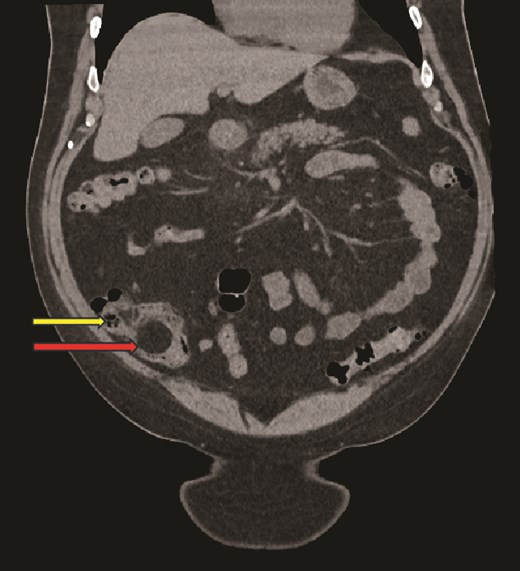

Computed tomography (CT) scan abdomen and pelvis was reported as follows: ‘Inflammatory phlegmon, fat stranding, free fluid, and reactive lymphadenopathy in the right iliac fossa. At the centre of the inflammatory phlegmon there is a dilated appendix with thickened walls. Small appendicolith at the base. Incidental note of a 3.2 cm caecal lipoma, which resides just below the ileocecal valve.’ (Figs 1–3).

Axial CT image showing caecal inflammation and peri caecal stranding (arrow).